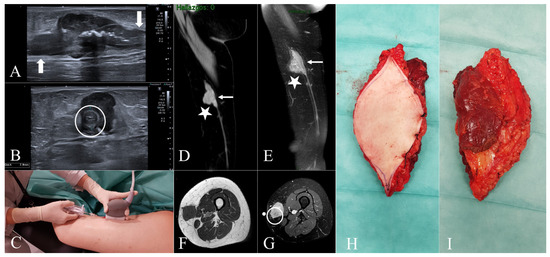

Figure 3.

Case 6. (A) = Clinical appearance of a woman with a large tumor on the inner aspect of her left ankle. (B,C) = Coronal T1-weighted and coronal T2-weighted, fat-suppressed MR images exhibit a giant subcutaneous lobulated nonspecific mass (blue arrows). In this case, continuity with vascular structures was not established, probably due to its large size. The lesion is in contact with tibial epiphysis, but no associated osseous changes were demonstrated. (D) = Specimen with marginal margin of resection. The skin island that includes the biopsy tract is identified; the ends of the great saphenous vein are indicated: proximal end (black arrow) and distal end (white arrow).